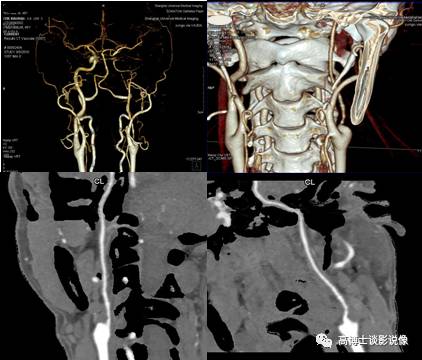

八、头颅血管CTA

头颅血管VR全容积重建,整体显示脑血管情况。薄层MIP及CPR显示动脉狭窄段的位置、形态,评估狭窄程度;评估血管斑块的性质及稳定性,了解有无继发血栓、侧枝循环建立等情况;为血管狭窄支架置入术后判断支架形态及通畅情况。此例显示:左侧颈内动脉近颈总动脉分叉处软斑形成伴局部管腔明显狭窄,左侧颈内动脉全程较右侧颈内动脉纤细。